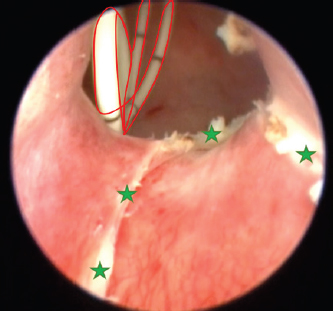

An orifice is found immediately where the urethra is formed; therefore, urine flows outward bypassing the urinary bladder and sphincter. Ectopy type is thought to be intramural due to visible thin mucous membrane partition between the bladder and ureter. It extends from the urethra to the anatomical ureter opening location. As seen in other ectopy cases, we observed a complex of pathologies: the urinary bladder was localized more caudally, and the urinary tract was shorter than usual (Fig. 2). Cystoscopy was performed with the instrument shown in Figure 3.

During the cystoscopy, a 1,000 ml injectable water bottle with disposable pressure infuser was used to expand and rinse the urinary tract. Findings were consistent with CT results. The urethra and bladder contained a mucous membrane tunnel which prevented the left ureter to open in a normal anatomic position. Instead, its orifice was shifted caudally straight into the urethra and not the trigone of the bladder.

Fig. 2. Post-contrast transverse reconstructed CT study images. Red stars indicate the left ureter opening into the urinary bladder. The blue arrow shows the contralateral ureter position. They both cross the wall of the bladder in a normal position, but the left one is excreting urine through a channel into the urethra. An orifice is found immediately where the urethra is formed; therefore, urine flows outward bypassing the urinary bladder and sphincter.